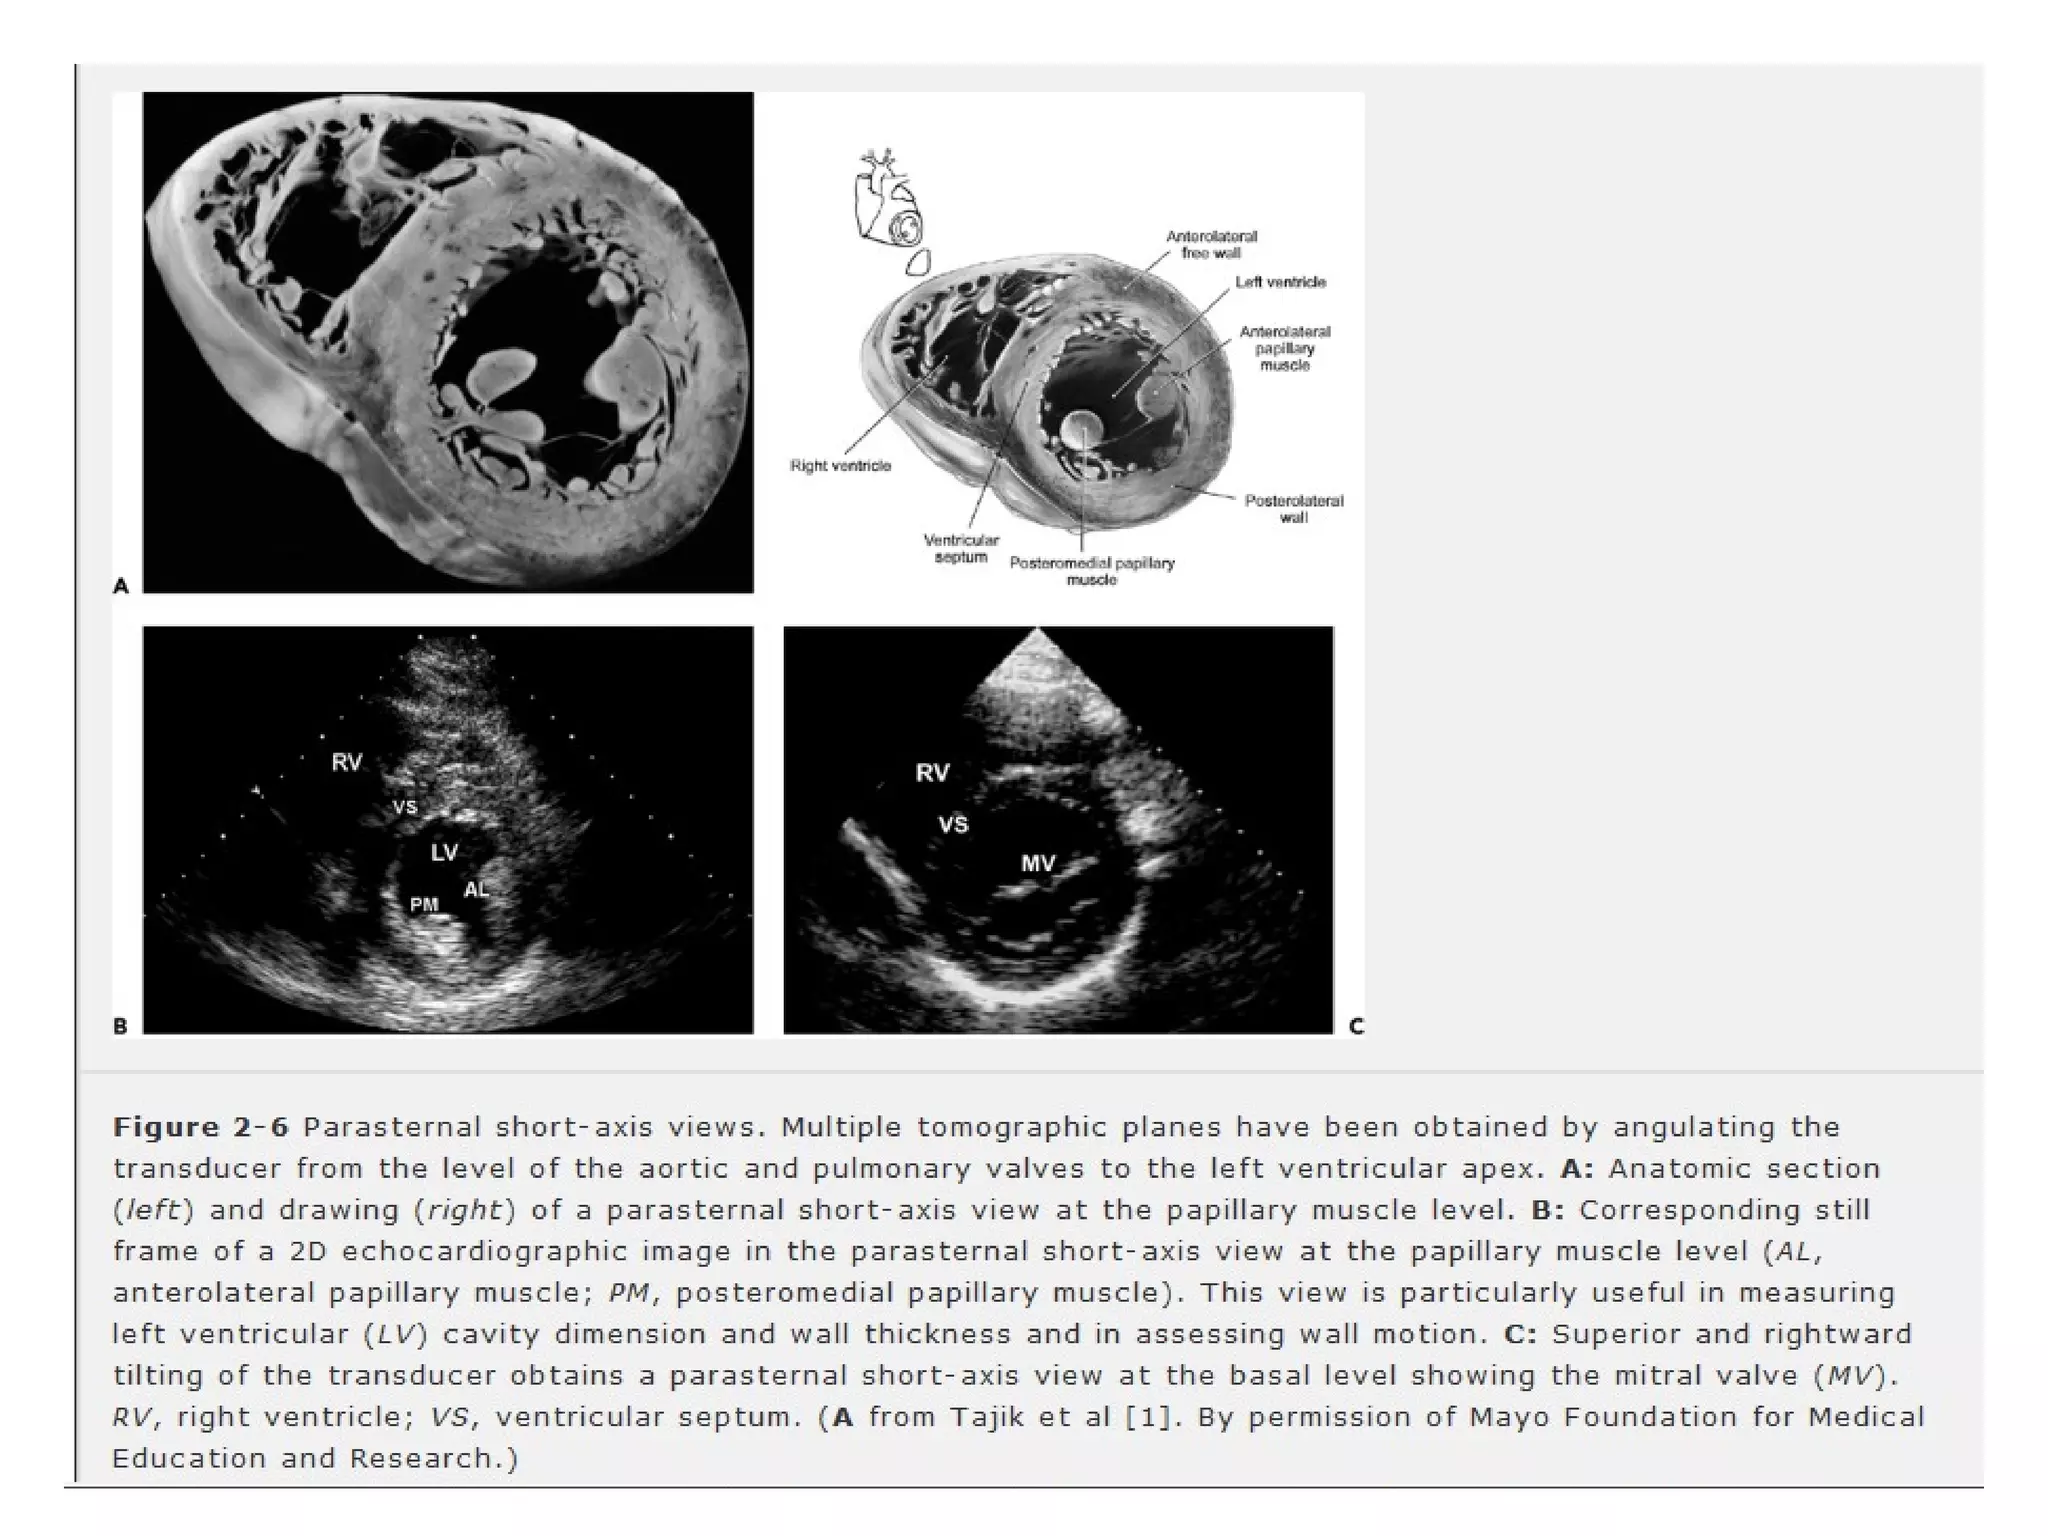

• clockwise rotation of 90 degrees

• Pts lateral wall I placed to the observer”s

right

• LV is displayed as if viewed from apex

• Apical level

• Papillary muscle level -

• Mitral valve level- Precise recording of

mitral orifice in pts with MS.

-Basal level- aortic annulus, AV, coronory

ostia, LA, TV, RVOT, PV & prox pa.